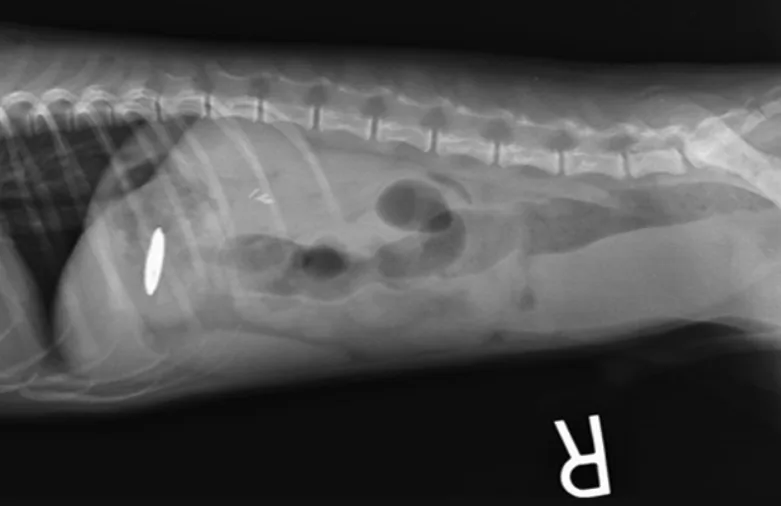

Zinc toxicosis can occur following ingestion of metallic foreign bodies (MFBs) that contain zinc, most commonly US pennies minted after 1982. Zinc ions and zinc salts are rapidly released from MFBs in the acidic environment of the stomach. The mechanism of toxicity is largely unknown but proposed to be due to oxidative damage resulting in hemolysis.1 MFB removal and supportive care are critical to recovery from zinc toxicosis.2

Zinc toxicosis is uncommon but should be considered in dogs with anemia and lethargy, especially with concurrent GI signs. Abdominal radiography and a thorough patient history (including vomiting of metal objects and ingestion of MFBs) should be performed rapidly.